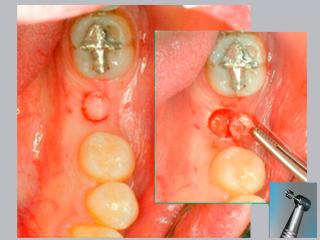

La solución a la falta de piezas dentarias se resuelve mediante procedimientos de microcirugía que permiten la reposición del diente ausente con una solución estética que lo hace imperceptible, aplicando los conceptos revolucionarios de Soft Tissue Integration e Immediate Function que implican la reposición de la pieza dentaria en el mismo procedimiento de instalación del implante optimizando tiempos y resultados, así como el establecimiento y mantenimiento de larga duración de la salud y estética de los tejidos blandos.

En este sentido nuestro consultorio desarrolla desde 1999 la técnica flapless prescindiendo del bisturí convencional y sin sutura, a través de una incisión circular de 5 mm de diámetro que garantiza un postoperatorio que pasa inadvertido y logra excelente resultado estético.

La técnica quirúrgica flapless (sin solapa) posee varias ventajas comparada con los procedimientos quirúrgicos convencionales, que incluyen la apertura de una solapa (flap) antes de la inserción del implante.